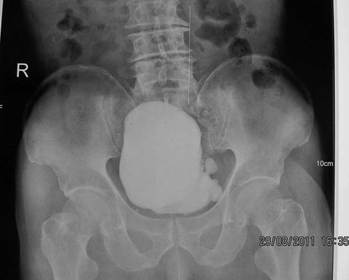

Prostatic Hypertrophy Prostate gland enlargement along with urinary output obstruction Common in males over 55 years of age Symptoms: reduced urine output along with sensation of full bladder Radiographic Appearance: borders of the bladder appear lumpy and irregular, base of the bladder has a notched appearance due to the enlarged prostate pushing up against it